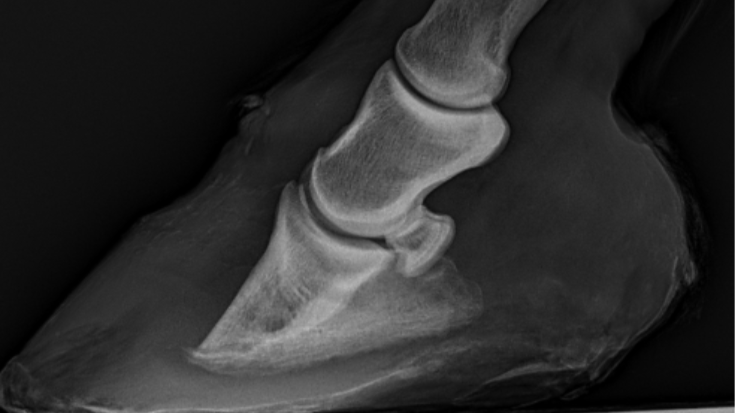

Warmbloedpaard met hoefabces

Anamnese 13-jarig warmbloedpaard. Het paard had twee maanden geleden een hoefabces rechtsvoor, dat aanvankelijk zeer pijnlijk was. Het abces werd uitgesneden, maar persisteert tot op...